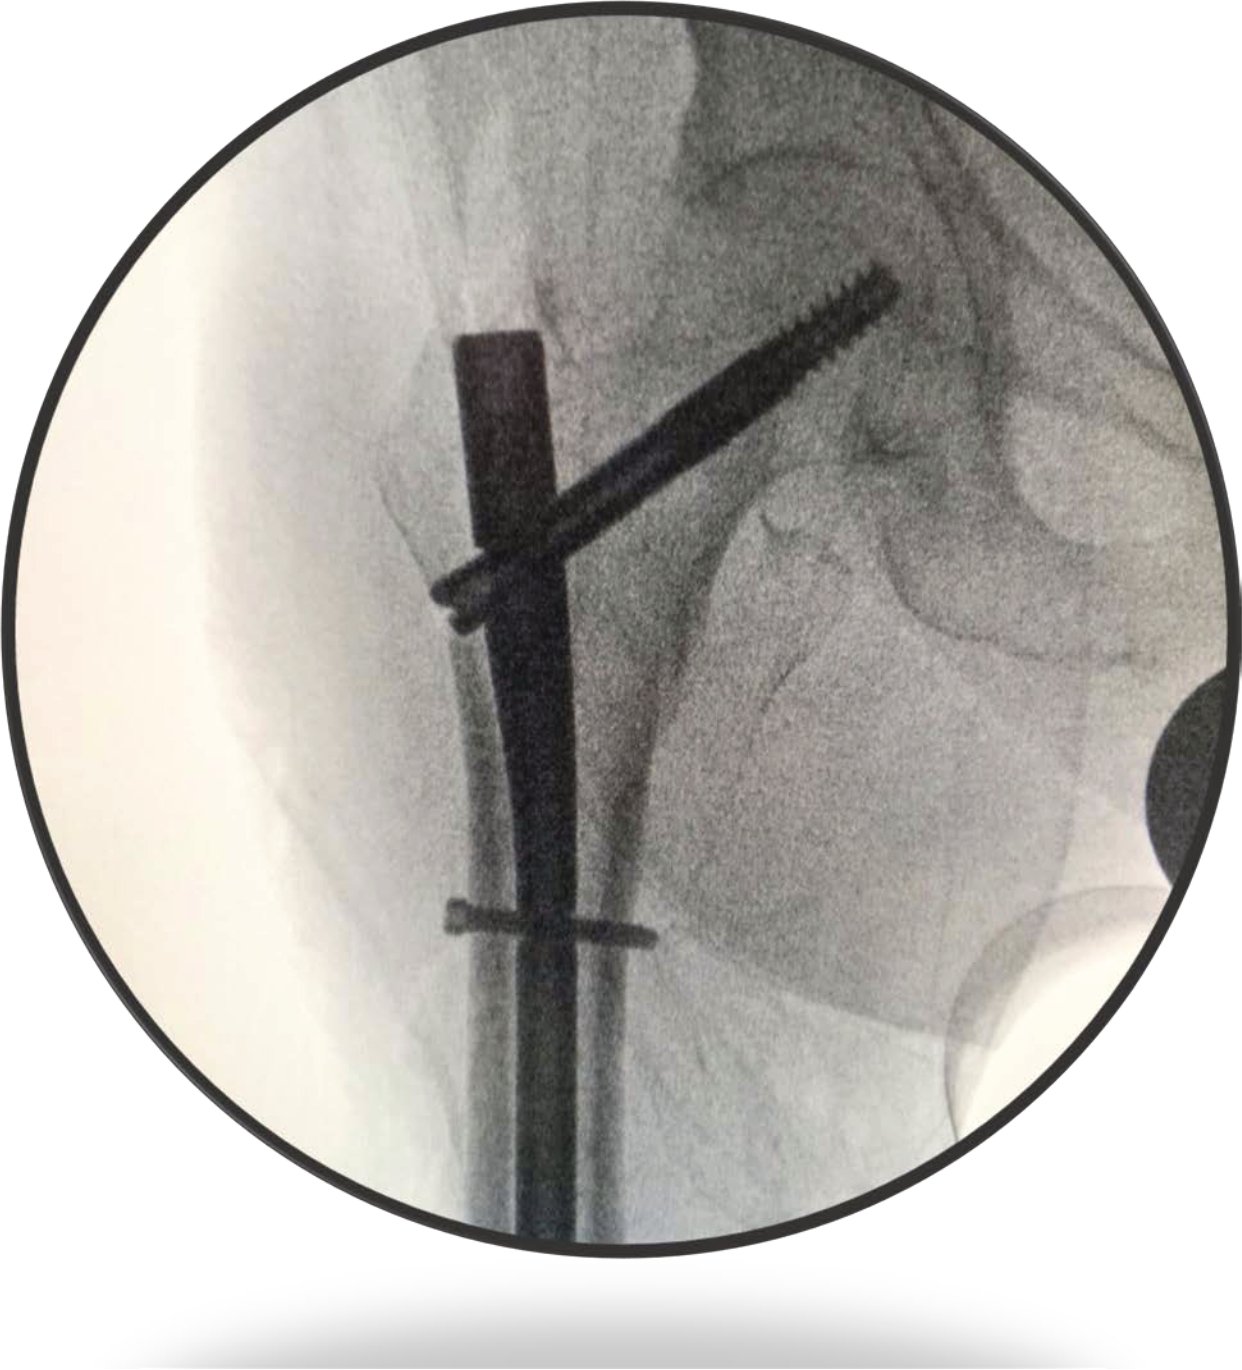

F1 Femorální hřeb krátký

F1 krátký femorální hřeb je specializovaný intramedulární implantát, který je vhodný pro všechny běžné typy trochanterických fraktur. Je vyroben ze slitiny titanu Ti6Al4V a jeho design klade důraz na minimalizaci invazivity a maximální přesnost. S parametry, jako jsou délky 170 a 190 mm a průměry 9, 10 a 11 mm, je tento hřeb účinným nástrojem pro stabilní fixaci.

Hřeb je vyroben z vysoce kvalitní a biokompatibilní slitiny titanu Ti6Al4V. Je dostupný ve dvou délkách, 170 mm a 190 mm, a třech distálních průměrech, 9, 10 a 11 mm. Proximální průměr činí 15,5 mm a úhly kyčelních šroubů jsou k dispozici ve variantách 120°, 125° a 130°.

Design hřebu zahrnuje menší průměr, což umožňuje minimalizovat vrtání při perkutánním vstupu. Je také vhodný pro použití u pacientů s velmi úzkými nebo vybočujícími femorálními krčky. Zjednodušená koncová krytka a systém stavěcího šroubu zvyšují účinnost operace. Hřeb o délce 170 mm je ideální pro vysoké umístění, což zajišťuje větší pevnost a přesnost. Hřeb o délce 190 mm je určen pro subtrochanterické rozšíření zlomenin. Design hrotu a drážky je navržen tak, aby redukoval pnutí na distálním konci hřebu. Boční zkosení snižuje podráždění šlach.

Distální zajišťovací šroub má unikátní závit: počátečních 75 % závitu je mělkých pro snadné vložení, zatímco koncových 25 % je hlubších, aby se zachytil laterální kortex a zabránilo se vyšroubování. K dispozici jsou varianty statického nebo dynamického distálního zajištění.